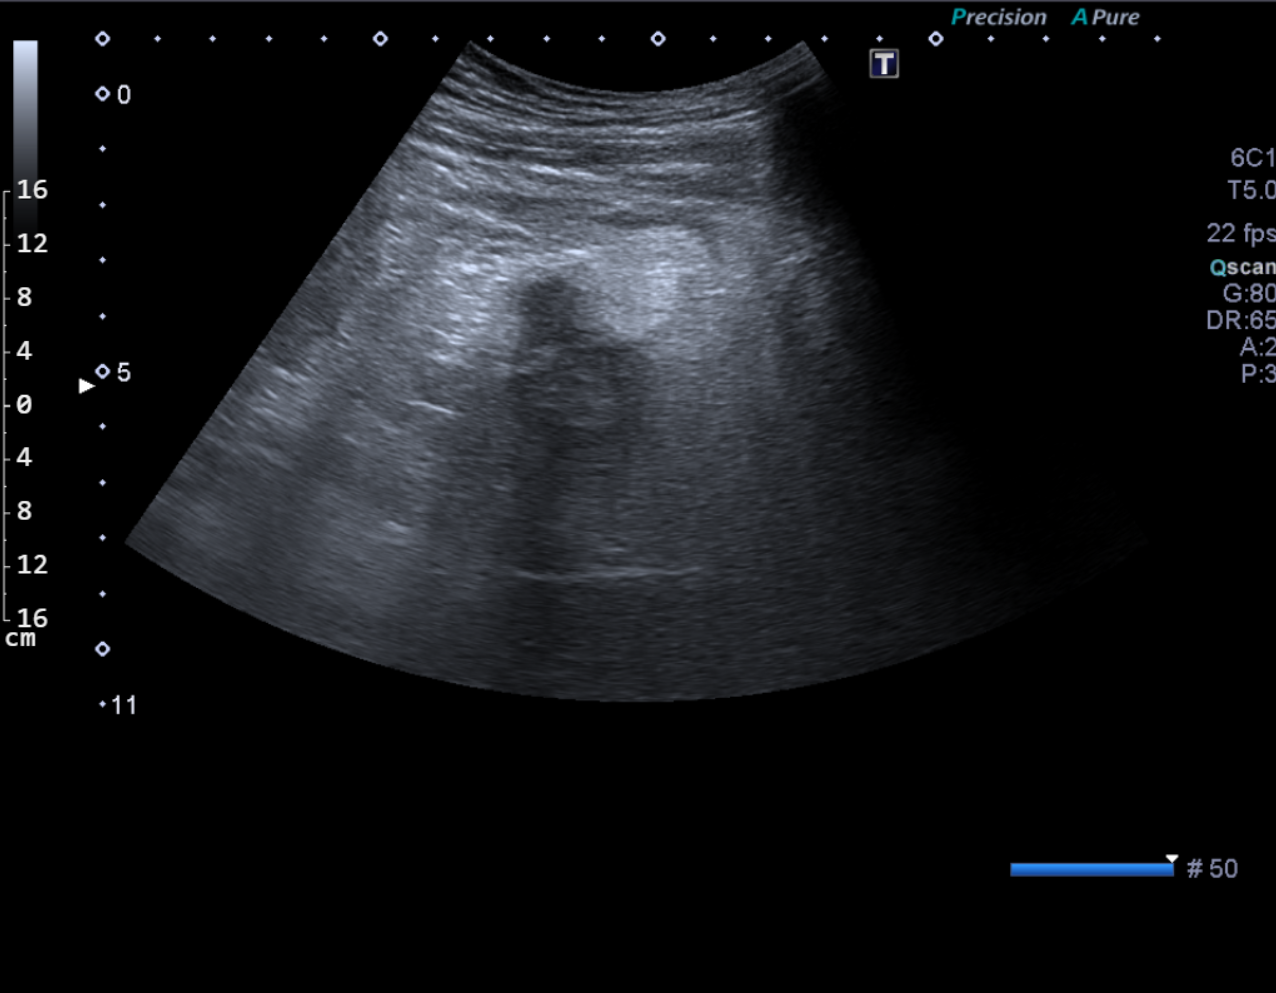

Vyšetření provádí erudovaný lékař, který pro danou vyšetřovanou oblast zvolí vhodnou ultrazvukovou sondu a nastaví optimální parametry přístroje. Pacient při vyšetření leží na vyšetřovacím stole a dodržuje pokyny lékaře. Nejčastěji se vyšetření provádí vleže na zádech, na břiše nebo na boku. Kůže pacienta se ve vyšetřované oblasti pokrývá vrstvou gelu pro sonografii. Lékař plynule pohybuje po pacientově těle ve vyšetřované oblasti ultrazvukovou sondou a při tom sleduje obraz na monitoru. Vyšetření se provádí v různých rovinách daných postavením sondy, někdy i v různých polohách pacienta. Během vyšetření lékař v případě potřeby provádí různá měření. Při vyšetření asistuje vyškolená sestra, která pomáhá především s odstrojením a uložením pacienta, provádí administrativní úkony a řídí objednávání pacientů. Před vyšetřením sestra nebo lékař vysvětlí pacientovi stručně, jak vyšetření probíhá a co je jeho cílem, eventuelně rozptýlí případné obavy pacienta z vyšetření. Na závěr vyšetření pak lékař pacientovi co nejsrozumitelněji vysvětlí zjištěný nález, jeho závažnost a případné další důsledky. Obrazová dokumentace je zhotovena tiskem na speciální papír, eventuelně je provedena digitální archivace obrazu.

Ultrazvukový přístroj